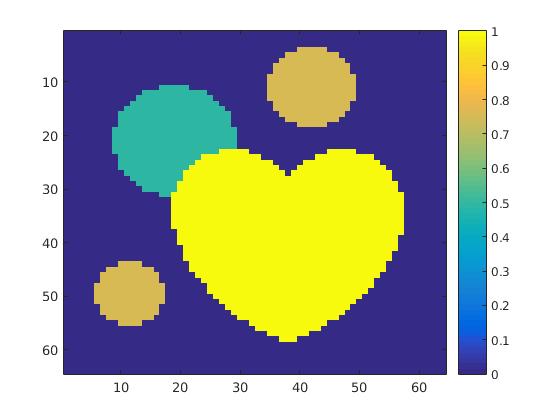

The first data set consists of a heart-shaped region and three circles on a static background (see figure 1 (a)). The two smaller circles are assumed to belong to

the same tissue type and therefore to the same subregion, which causes a total of four subregions, including the background. To simulate a more realistic application of dynamic SPECT

imaging, we used a synthesized representation of a rat liver as a second data set (see figure 1 (b)). The temporal concentration curves used to simulate the data sets

are shown in figure 2. As before, the total number of subregions was chosen to be equal to four in order to provide a both simple and realistic shape model.